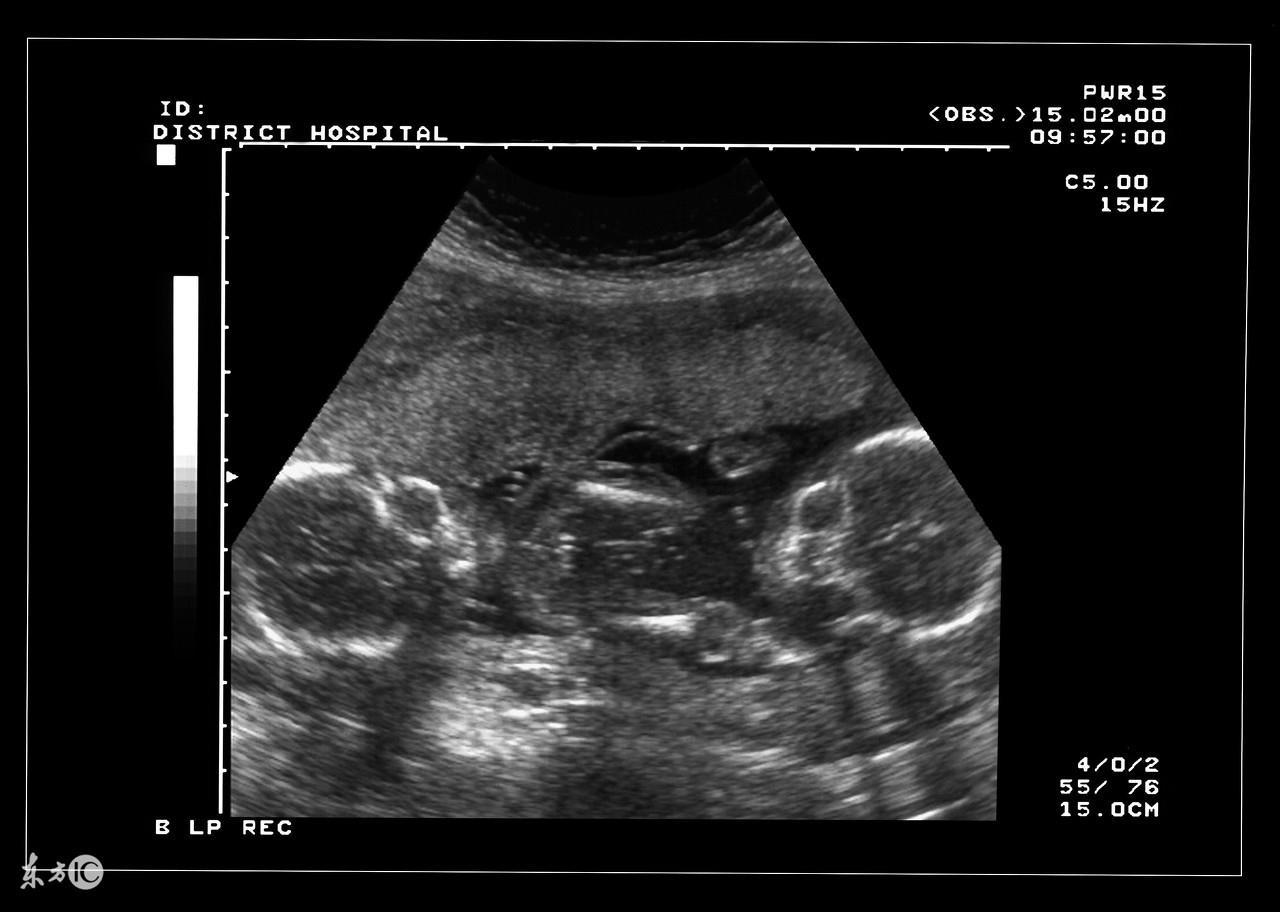

双胞胎确实是一件可想而不可求的事情,当孕妇怀上双胞胎或者多胎后,使母体长期处于超负荷的状态,在预产期到来之前,准妈妈需要就是否实施剖腹产的问题预先与家人和医生达成一致,并为此做好准备。大家都知道,自然分娩是最理想不过的,但实际上为了确保安全,大部分多胞胎最终实施的都是剖腹产。

双胎妊娠检查非常重要。由于双胎孕妇比一般孕妇子宫明显增大,这不仅增加了孕妇身体的负担,还由于对其心、肺及下腔静脉的压迫而容易产生心慌、呼吸困难及下肢浮肿等不适。双胎妊娠出现妊娠合并症者也较多,其妊高娠的发生率明显高于一胎妊娠,所以双胎妊娠者要听从医嘱,按期去医院接受检查。

双胎妊娠由于子宫腔相对狭窄胎盘血液循环障碍,其流产发生率较单胎妊娠高2—3倍,因此应加强孕期保护与监护。若一胎发生死胎,另一胎仍可继续生长发育,死亡的胎儿将被吸收或挤压成纸样儿随正常胎儿娩出,不必担心害怕,更不要引产终止妊娠。因双胎妊娠子宫过度膨胀,易发生早产,故应于中期妊娠后注意休息,避免房事,并提前4周做好分娩前的准备工作。由于妊娠的并发症尤其是妊高娠的发生率比较高,从母子安全考虑,应在预产期即住院待产,以免发生早产或其他不测。